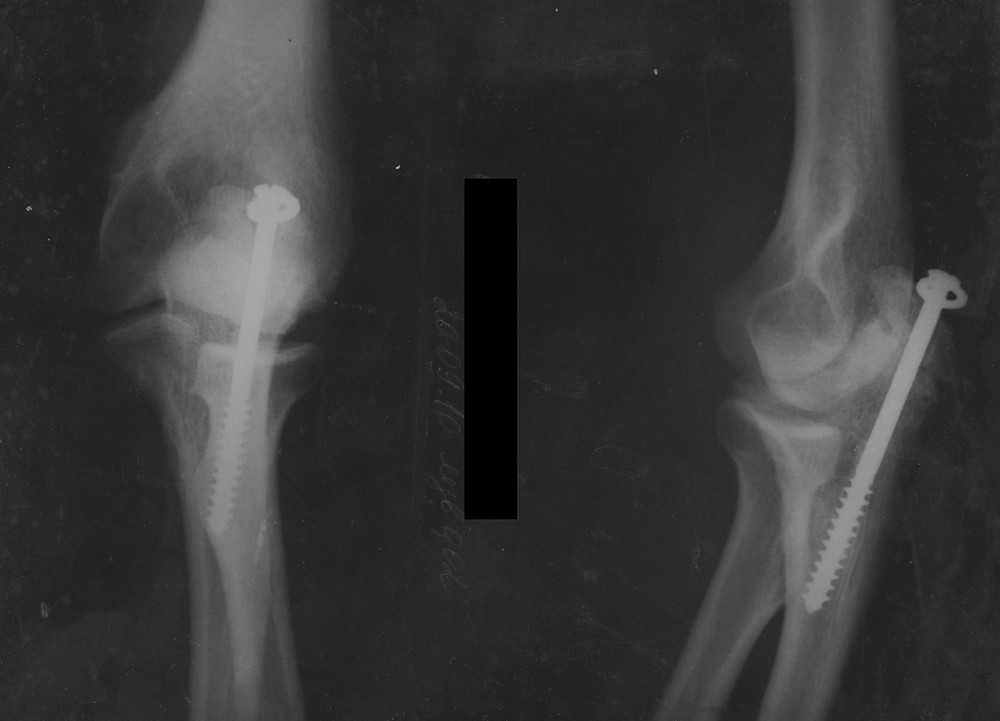

Re: Ложный сустав локтевого отростка

Обещанные снимки.